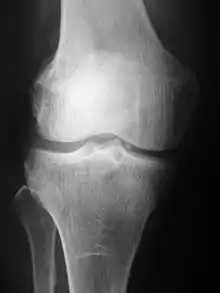

Plain radiography was the only imaging modality available during the first 50 years of radiology. Due to its availability, speed, and lower costs compared to other modalities, radiography is often the first-line test of choice in radiologic diagnosis. Also despite the large amount of data in CT scans, MR scans and other digital-based imaging, there are many disease entities in which the classic diagnosis is obtained by plain radiographs. Examples include various types of arthritis and pneumonia, bone tumors (especially benign bone tumors), fractures, congenital skeletal anomalies, and certain kidney stones.